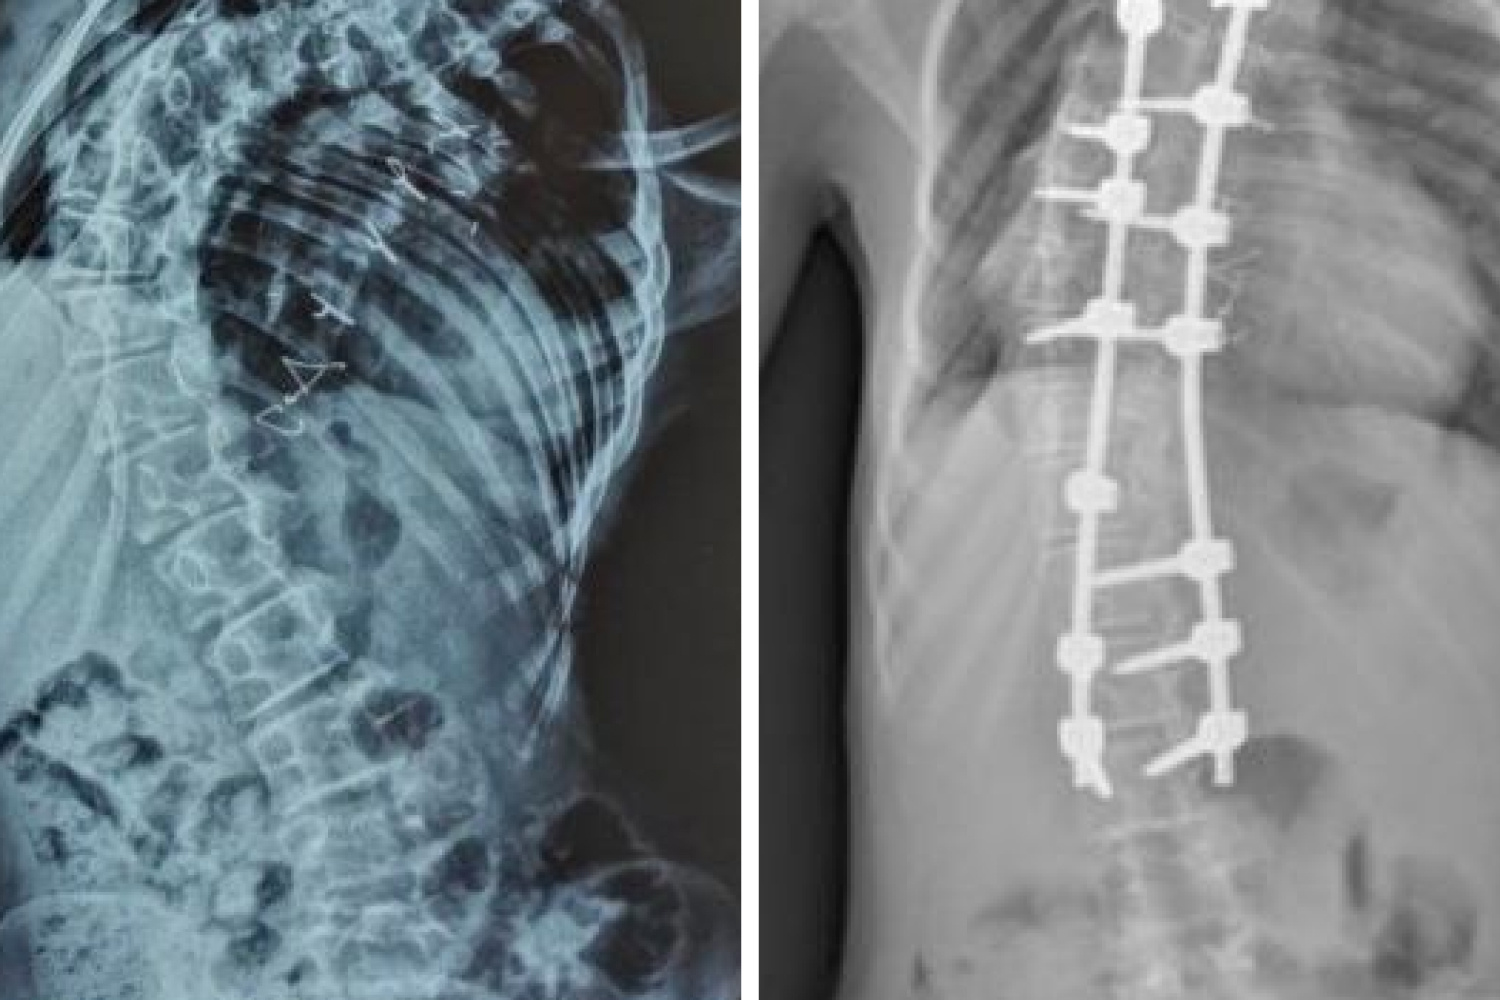

Сколиоз прогрессировал стремительно, а плечевой пояс был перекошен. Левое плечо было на 10 сантиметров ниже правого, наблюдался ярко выраженный реберный горб. Из-за этого у девочки развилась дыхательная недостаточность. Подробности операции рассказал Андрей Пантелеев, хирург-вертебролог отделения травматологии и ортопедии РДКБ:

— В тела позвонков со второго грудного по третий поясничный мы установили транспедикулярные винты, которые впоследствии соединили между собой стержнями. Затем постепенно изменили ось позвоночника в трех плоскостях, за счет чего и добились коррекции. Последним этапом на протяжении металлоконструкции уложили костный аутотрансплантат, чтобы обеспечить ее максимальную стабильность в будущем.

Хирурги выполнили задачу, выровняли плечи и убрали горб. Таким образом, девочке стало легче дышать. Сейчас она уже восстановилась после операции.